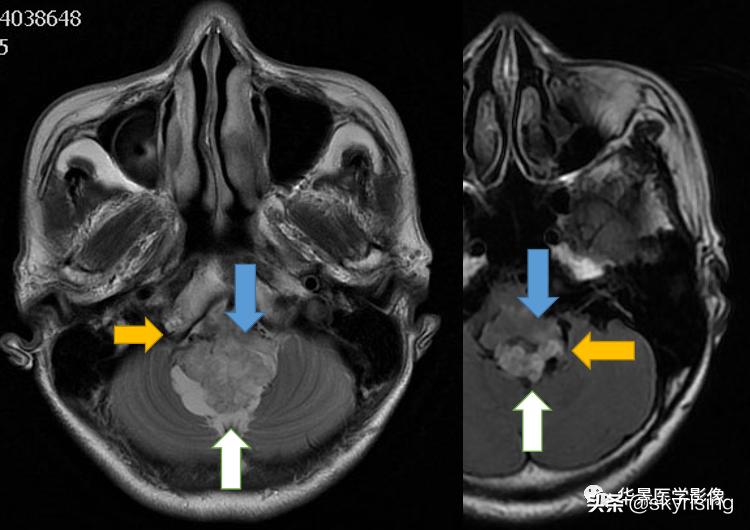

上图白色箭头:小脑延髓池内延髓背侧不规则形团块影,不均长T2信号,FLAIR条片样信号减低,提示水分子含量高。

蓝色箭头:注意病灶与延髓边界不清,不除外来源或侵及延髓。

黄色箭头:右侧细小流空血管信号;左侧较粗大贴边流空信号血管影。

上图白色箭头:小脑延髓池内延髓背侧不规则形团块影,延髓受压变形。

黄色箭头:走行与病灶边缘的流空信号血管影。

黄色箭头:病灶边缘见流空信号血管影。

上图白色箭头:病灶呈DWI低信号,ADC高信号,信号欠均,提示弥散不受限。